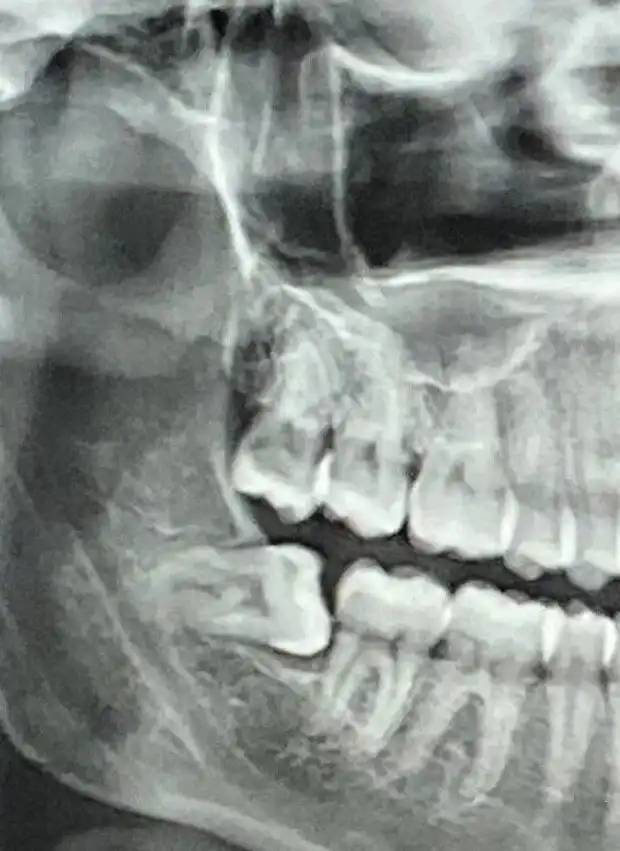

Сегодня я узнал, что мой зуб мудрости растёт неправильно